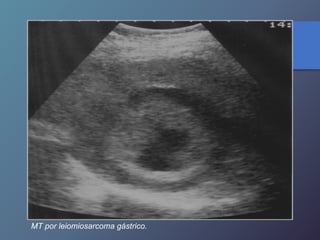

MT por leiomiosarcoma gástrico.